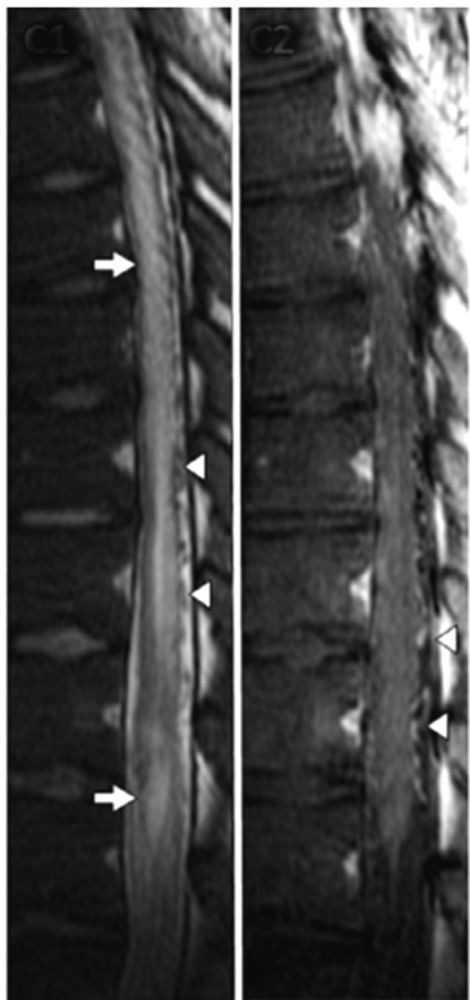

Q10: 41 year old patient presents with a rapid onset of paraplegia. He is found to be HIV positive. CSF shows elevated total protein (0,8 g/L), a mild pleocytosis (19 lymphocytes/µl), and a glucose value of 3.2. Oligoclonal bands were negative. T1 weighted s.